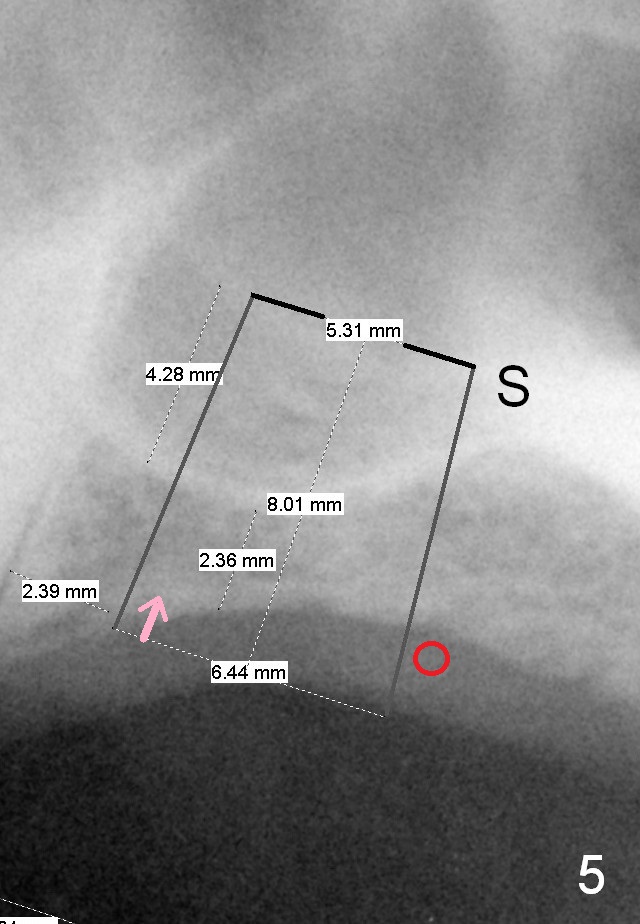

A 60-year-old man requests implant at the site of #14 (Fig.1,2, opposing a natural tooth (Fig.7)). Although bone height is limited, bone density appears high with sinus septi (S and arrowheads). The ridge seems to be wide clinically; implant will be as wide as possible. An envelop incision will be made to get the best visibility (as compared to tissue punch). At entry point, the bone height is 2.5 mm (Fig.3 red line); as the implant or osteotomy diameter increases, bone contact enhances (pink lines). If lateral window approach is adopted, a longer implant will be chosen (14 mm in Fig.3 vs. 11 mm in Fig.4, both tissue-level). The stronger distal septum may deviate the apical portion of the longer implant (Fig.3 arrow).

Another set of choice will be bone-level implants (SM and UF). The advantage of the former is its taper; the difference of the base and apex diameter is 1.1 mm (Fig.5 vs. 0.6 mm for UF (Fig.6)). It appears that a smaller parallel-walled drills can be used for the former (underprep) so that primary stability is more easily achievable. But according to the manufacture, the design of the latter allows the threads to be more aggressive. The surface treatment of the latter is more advanced (hybrid sand blast & acid etched vs. resorbable blast media; osseointegration occurs quicker for the latter). Which implant is finally chosen?